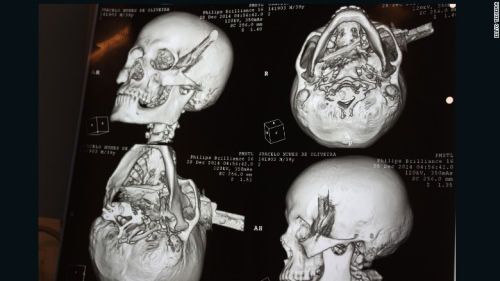

男子被人用刀刺中頭部,直穿頭骨。

中新網(wǎng)1月4日電 據(jù)外媒報道,巴西一名男子在與他人爭吵過程中被人用刀刺中頭部,直穿頭骨。在經(jīng)過2個半小時的手術(shù)后,該男子奇跡存活。

據(jù)報道,39歲受害男子系一名出租車司機,事發(fā)時他正在一個酒吧喝酒,結(jié)果與人發(fā)生口角。男子被刺中4刀,其中3刀刺中身體,1刀被插進頭部,橫穿過左眉骨。

醫(yī)生說,刀已經(jīng)完全穿過了男子的頭部,幾乎就要接近嗅覺神經(jīng),但僅僅破壞了部分味覺神經(jīng)。男子幾乎就要失去視覺、嗅覺和味覺,但是沒想到,幸運的是他將毫發(fā)無損。